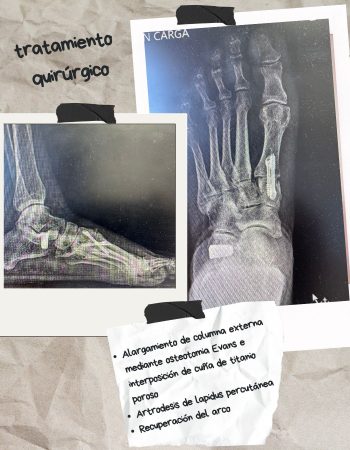

En este caso se decidió realizar una osteotomía varizante de calcáneo con la que llevamos el talón hacia dentro corregiendo el talo valgo y permitiendo un mejor brazo de palanca del Aquiles.

Además de eso realizamos una artrodesis cuneometatarsiana del primer radio, conocida como artrodesis Lapidus debido a los signos de inestabilidad que presentaba en la radiografía en carga. De esta forma, estabilizamos el primer radio del pie a la vez que corregimos la supinación del antepie, deformidad frecuente tras la corrección del retropie.

Ambas técnicas se realizaron mediante cirugía percutánea, con pequeñas incisiones que evitan una cicatriz amplia y dolorosa y mínima los daños a los tejidos y el dolor postoperatorio.